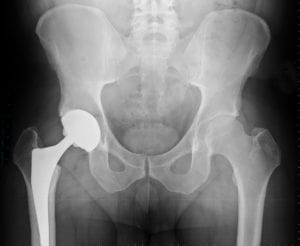

Deciding to Have Joint Replacement Surgery

If you are thinking about having joint replacement surgery, you most likely have been told by your orthopedic specialist that conservative therapies are no longer sufficient in keeping your pain under control so that you can do the things you want to do. This pain is likely caused by Read More

If you're up for joint replacement surgery, you’re not alone. Roughly a million Americans undergo joint replacement surgery every year. While there are many alternatives for treating joint problems, joint replacement is sometimes the last and only option that can bring lasting pain relief and Read More

Recovery From A Total Joint Replacement Surgery

If you are dealing with persistent joint pain and a limited range of motion, you may be considering total joint replacement surgery. Total joint replacement surgery is a procedure that helps to relieve chronic joint pain and improve mobility when other treatments have been unsuccessful. Joint Read More